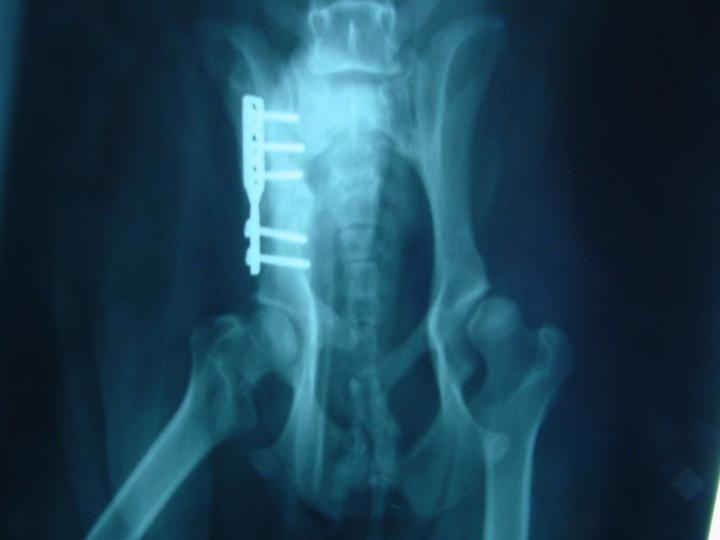

- Post-Cirurgia

Após a intervenção cirúrgica e control radiográfico durante as primeiras vinte e quatro horas os animais foram mantidos sob, antibióticos, antiinflamatórios não esteroides e morfinicos. Foram entregues aos proprietários nas 48 horas que se seguiram com as seguintes recomendações: aplicação de clindamicina (10 mg/Kg Po 12/12 horas) e Rimadyl (4mg/Kg) durante 7 dias.

Durante o primeiro mês aconselhou-se exercÃcio limitado e passeio à trela. Ao 2º e 3º mês foi progressivamente tomando a actividade normal. Observamos que no controlo radiológico imediato a cobertura acetabular se corrige muito pouco. Só ao fim de 4 semanas é que começamos a verificar um aumento da cobertura acetabular.